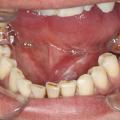

L’examen clinique avec palpation bidigitale (ou bimanuelle) permettra alors de retrouver le calcul dans le conduit submandibulaire (fig. 3 et 4).

• sialodochite : elle se caractérise par une fièvre élevée, une douleur vive et aiguë, irradiant à l’oreille, associée à une dysphagie voire une hypersialorrhée. On retrouve du pus à l’ostium (fig. 7) ;

Examen physique

L’inspection exobuccale recherche un gonflement de la glande. L’inspection endobuccale recherche une crête salivaire inflammatoire, une issue de salive ou de pus à l’ostium.

La palpation de la glande confirme le gonflement, alors que la palpation bidigitale de la glande et du conduit pratiquée d’arrière en avant (pour éviter de repousser un calcul vers le hile) recherche un calcul.